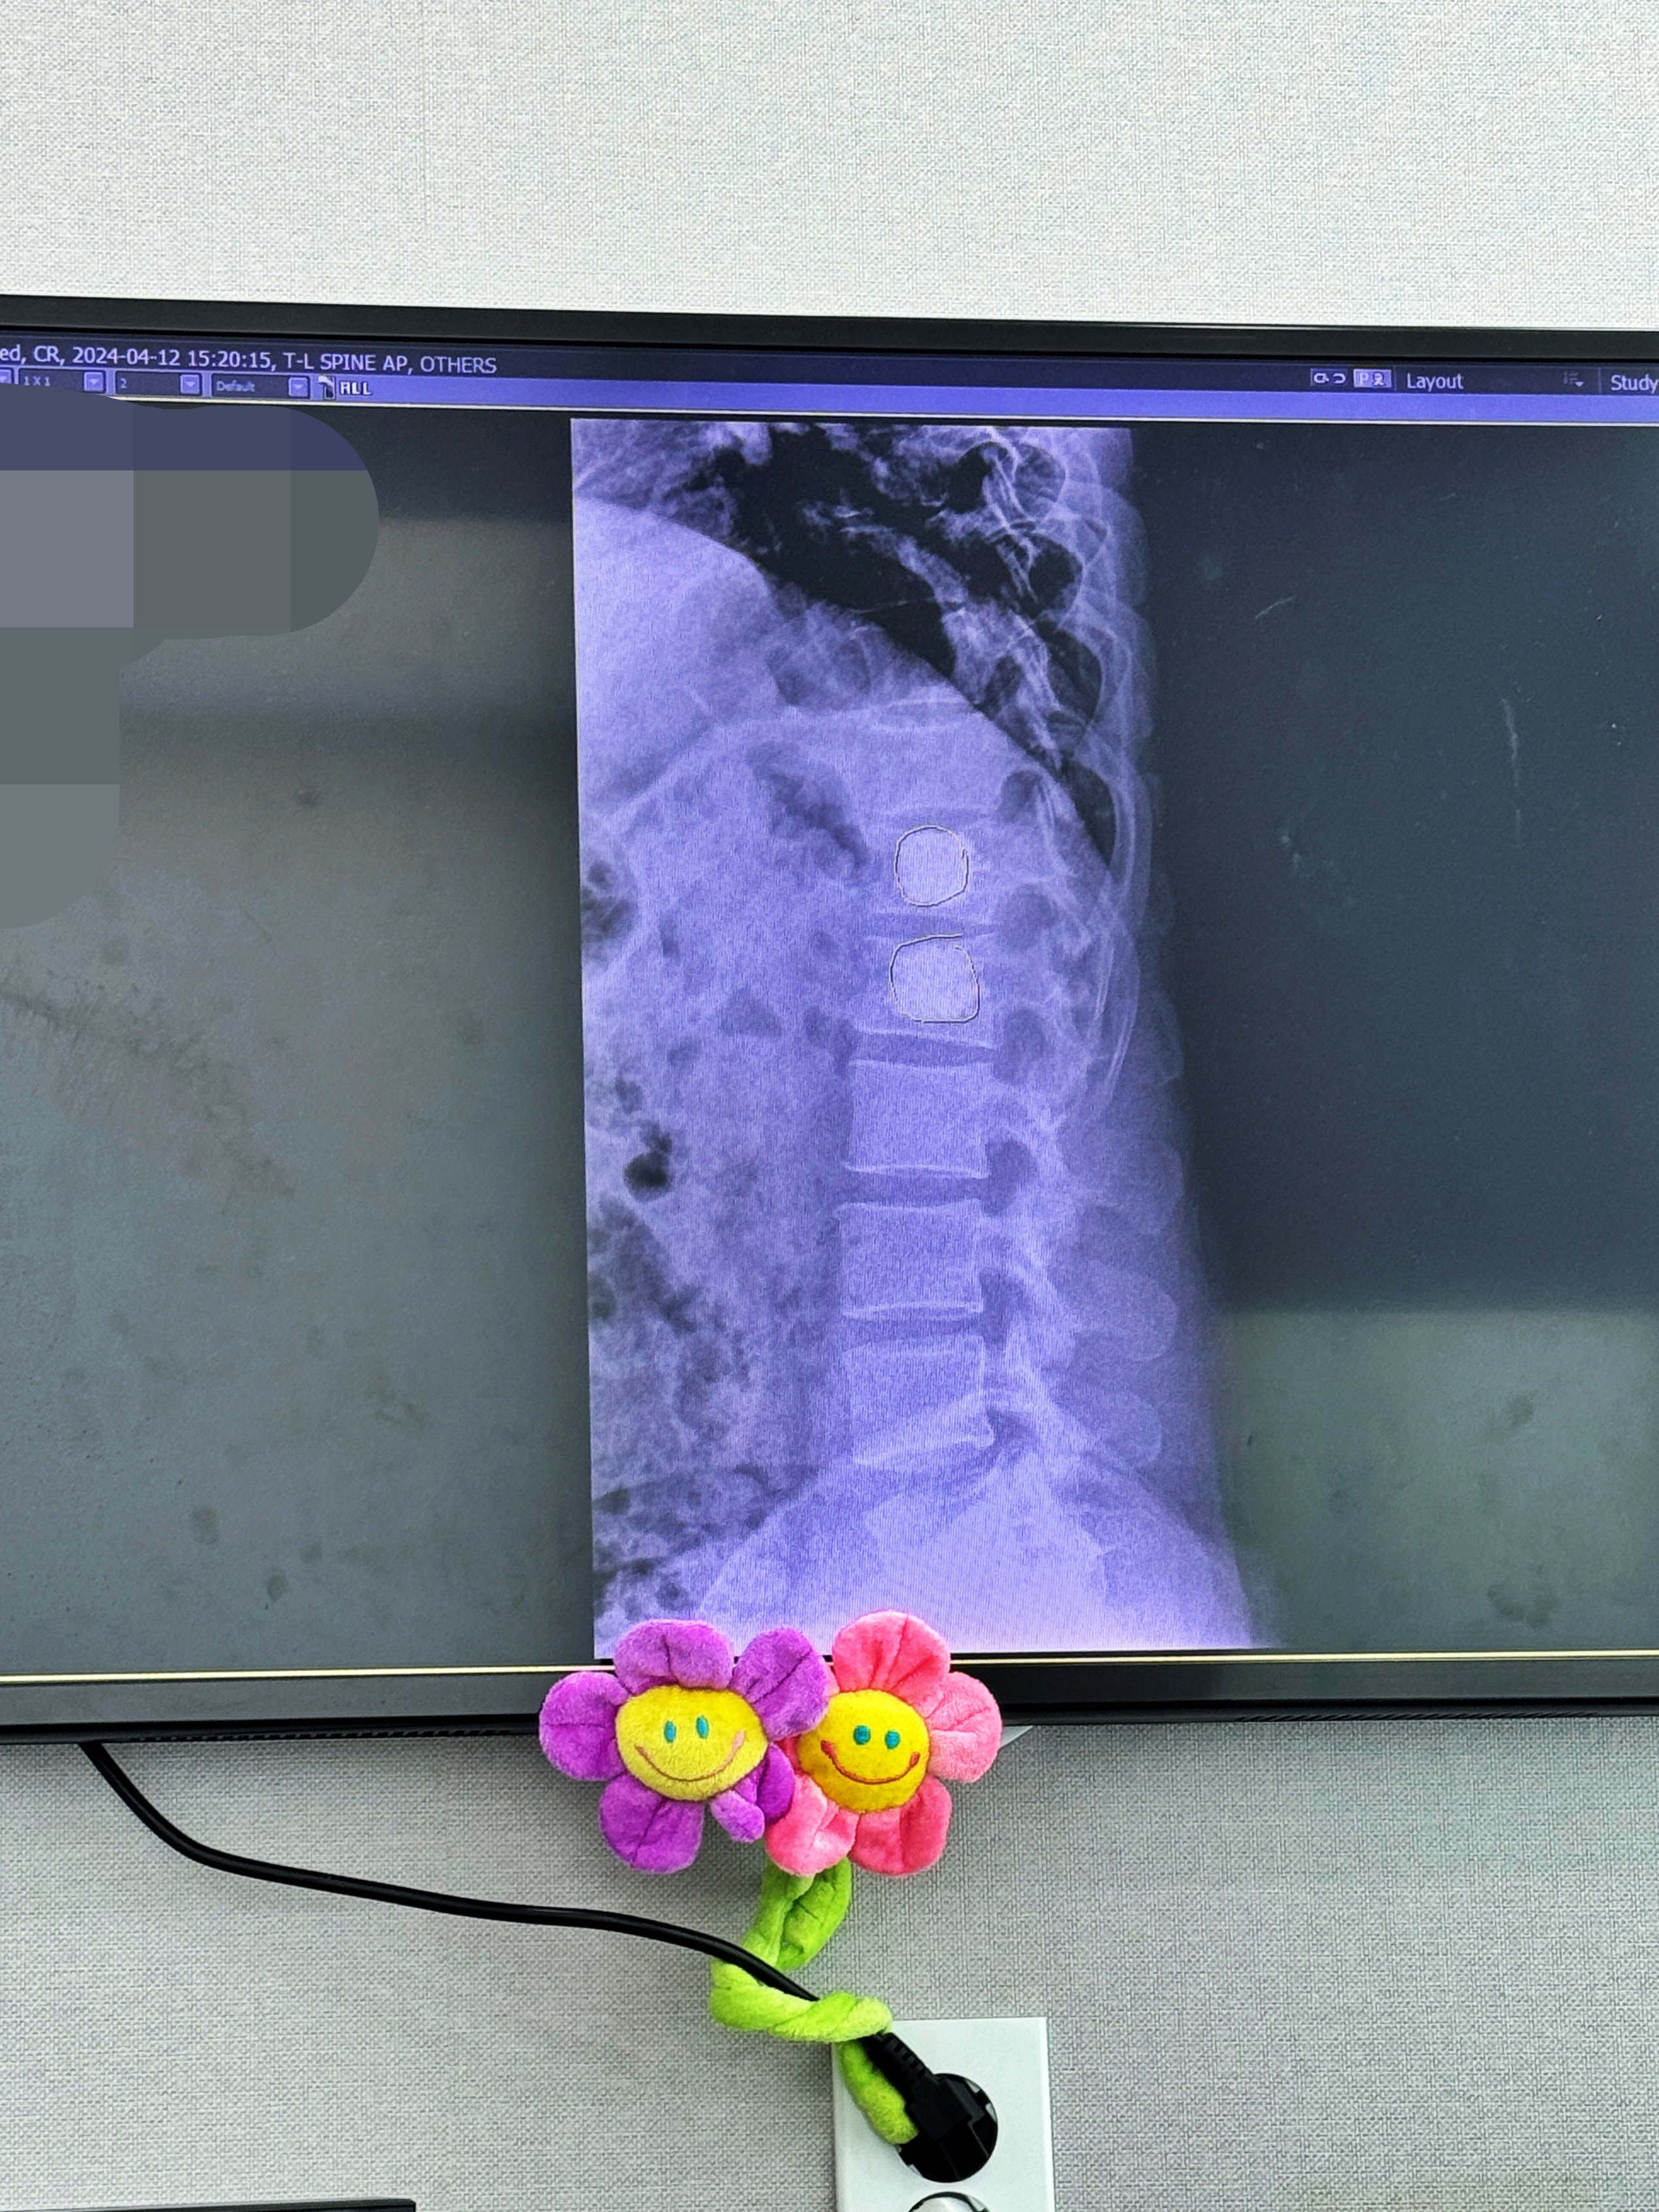

외래예약을 3시 50분으로 잡아줬습니다만, X-RAY 촬영도 있기에 약 30여분 빨리 도착하여 먼저 영상의학과로 향했습니다. 외래진료를 보기 위해 내원하여 대기하는 사람들도 많았고요.

X-RAY 촬영은 금방 끝납니다.

특유의 시끄러운 소리가 일품인 MRI나, 시끄럽지는 않지만 지루함의 연속인 CT 촬영에 비하면 간단하지요. 사진 두 장을 찍고 진료실 앞에서 제 차례를 기다립니다. 진료실에는 3시 45분쯤 들어갔습니다. 대략적인 예약시간에 맞게 들어가게 되는군요.

모니터에 보이는 X-RAY상에 동그랗게 표시한 부분이 골시멘트입니다.

넣을때는 좀 아팠지만 수술 다음날 일어나니 거짓말처럼 뼈에서 느껴지는 통증은 사라졌습니다. 다행히 경과도 좋고 일상생활에서 느껴지는 통증이 있는지 물어보시는데 일상생활에 지장이 없고 가끔 아프다 안 아프다 한다고 하니 무거운 물건만 들지 말고 당분간 조심하면 일을 해도 상관 없을 것 같다고 하시네요.